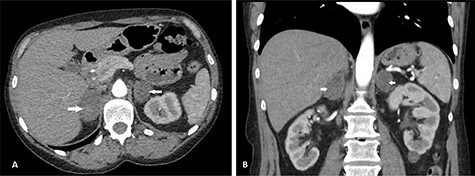

She had sequential CT and ultrasound scans to monitor her adrenal hemorrhages. Adrenal artery embolization was considered in the event of a rebleed and the patient was pre-emptively counseled accordingly. Her hematomas however remained stable on her scans. She had serial hemoglobin monitoring and did not require blood transfusion. She had a heparin-induced thrombocytopenia (HIT) screen on Day 8 on admission and this was negative. She was therefore, managed conservatively and discharged after 11 days. At discharge, she was placed on a reducing dose of oral hydrocortisone to reach target maintenance doses of 10 mg in the morning, 5 mg at noontime and 5 mg at bedtime. She was discharged on fondaparinux and her warfarin was restarted after 5 days when her platelet counts normalized. She had a repeat CT scan 6 weeks post discharge, which showed slow resolution of her hematomas with no underlying mass (Fig. 2).

CT scan after 6 weeks showing axial (A) and coronal (B) views of resolving BAH (arrows). The right adrenal hemorrhage now measures 30 × 46 mm axially and the left adrenal hemorrhage measures 33 × 28 mm.